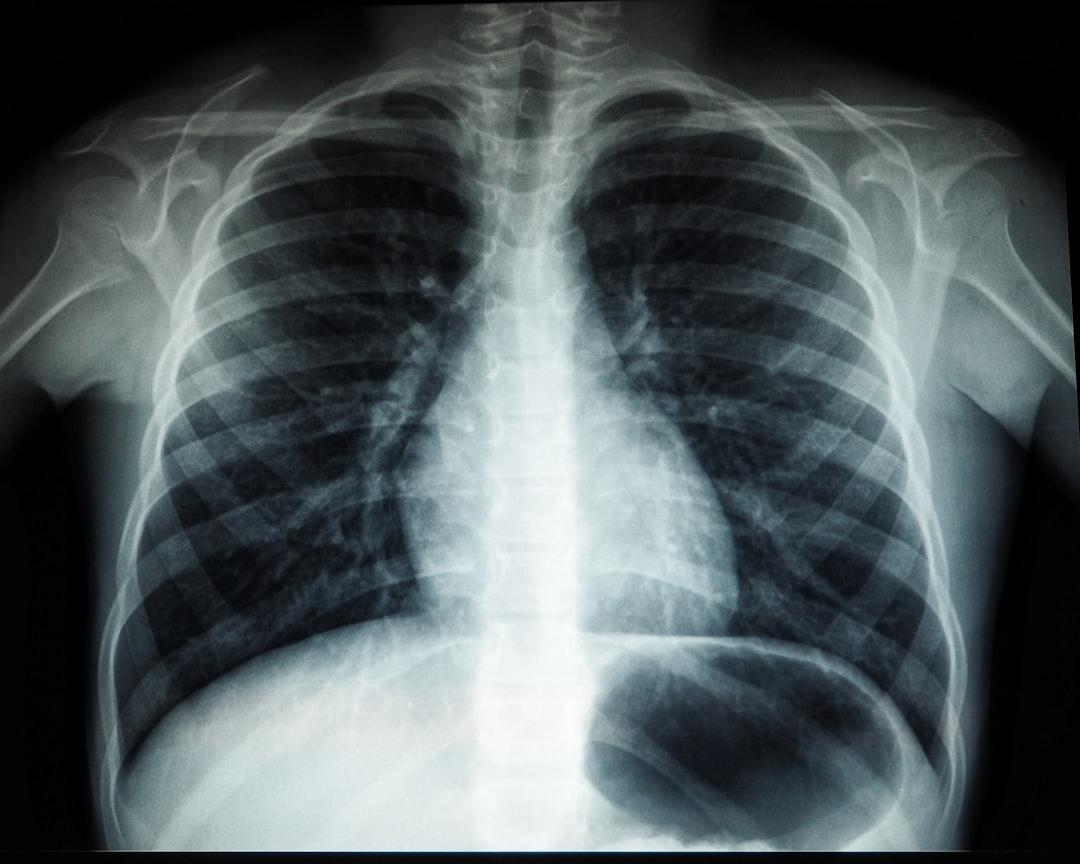

İzmir Göğüs Doktoru arayışında olan hastalar için doğru tanı ve etkili tedavi, solunum sistemi hastalıklarının kontrol altına alınmasında kritik bir rol oynar. Akciğerler ve solunum yolları, vücudun oksijen ihtiyacını karşılayan hayati organlardır ve bu sistemde meydana gelen en küçük bir sorun bile günlük yaşam kalitesini ciddi şekilde etkileyebilir. Göğüs hastalıkları, yalnızca öksürük veya nefes darlığı gibi basit şikâyetlerden ibaret olmayıp, erken tanı konulmadığında hayati risk oluşturabilen ciddi hastalıkları da kapsamaktadır.

Göğüs hastalıkları; akciğerler, bronşlar ve solunum yollarını etkileyen geniş bir hastalık grubunu içine alır. Bu hastalıkların büyük bir bölümü erken dönemde teşhis edilmediğinde ilerleyici seyir gösterebilir ve kalıcı hasarlara yol açabilir. Bu nedenle uzman bir göğüs hastalıkları doktoru tarafından değerlendirilmek, hastalığın seyrini olumlu yönde değiştiren en önemli faktörlerden biridir. İzmir’de uzun yıllara dayanan klinik ve akademik deneyimiyle öne çıkan Prof. Dr. Ayşe Aktaş, göğüs hastalıkları alanında kapsamlı tanı ve tedavi hizmetleri sunarak hastalarına güvenilir bir sağlık desteği sağlamaktadır.